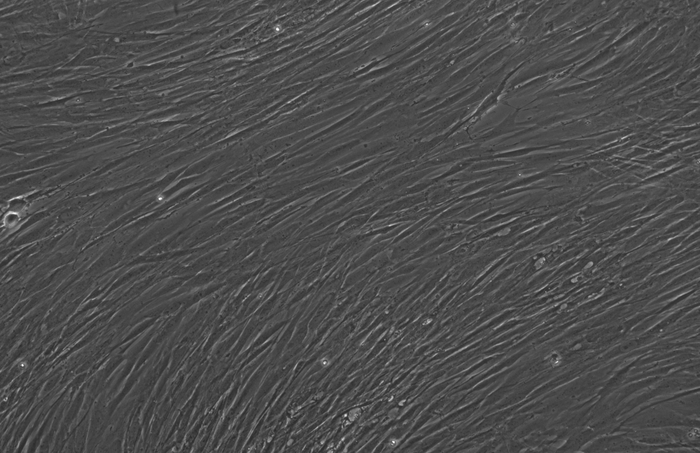

下面这三张图展示的是,OpenAI设计的蛋白质能更高效地诱导干细胞重编程:

使用RetroSOX与RetroKLF变体(结合OCT4, MYC)重编程10天后,出现了大量具有紧凑、圆形形态的集落,这是细胞迈向iPSC状态的典型特征

为了进一步确认重编程效率的提升并探索其临床应用潜力,研究团队测试了一种新的递送方式(使用mRNA替代病毒载体)和另一种细胞类型——源自三位中年(50岁以上)捐赠者的人类间充质基质细胞(MSCs)。

仅7天内,便有超过30%的细胞开始表达关键的多能性标记物(SSEA4和TRA-1-60)。

到第12天,已出现大量形态与典型iPSC相似的集落。这些细胞中超过85%激活了包括OCT4、NANOG、SOX2和TRA-1-60在内的关键干细胞标记物的内源性表达。